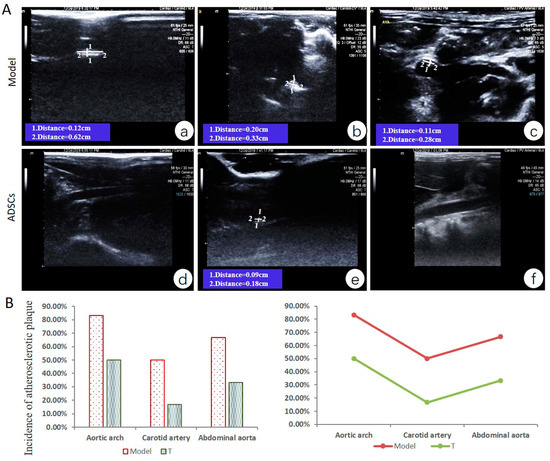

3.3. ADSC Transplantation Alleviates Atherosclerotic Plaque Formation in AS Rabbits

3.4. ADSC Transplantation Reduces the Size of Aortic Atherosclerotic Lesions in Rabbits